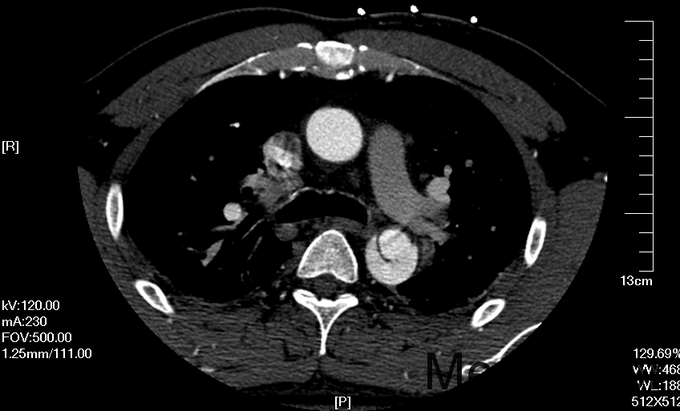

入院查体:体温36.5℃,脉搏90次/分,规则,呼吸18次/分,规则,血压150/80mmHg,胸廓正常,无胸骨叩痛。呼吸运动正常,语颤正常,无胸膜摩擦感,无皮下捻发感,叩诊正常清音,肺下界正常,双肺呼吸音粗,呼吸音对称,无罗音。心音可,心率90次/分,无杂音,腹部无压痛,无反跳痛,肝肋下未及,胆囊无压痛,Murphy征阴性,脾肋下未及,肾区无叩痛,双下肢不肿。入院后完善相关检查(胸腹主动脉CTA:主动脉夹层动脉瘤;两侧胸腔少量积液。)

予以诊断:1.主动脉夹层动脉瘤;2.高血压3级,极高危组。诊断明确后行“左颈总动脉-腋动脉转流手术+胸主动脉覆膜支架腔内隔绝术”。左侧颈部切口,游离出左侧颈总动脉,左侧锁骨下动脉,左侧椎动脉等分支。使用8mmG-tex血管一端与左锁骨下动脉行端侧吻合,G-tex血管另一端与左侧颈总动脉行端侧吻合。经右侧股动脉入路造影见主动脉夹层,破口位于左锁骨下动脉开口医院0.5cm处。左锁骨下动脉近端封闭,桥血管通畅,腋动脉及左侧椎动脉血流良好。置入美敦力胸主动脉覆膜支架(28*157mm),定位后释放。造影见胸主动脉支架释放良好。

主动脉夹层为大血管急诊,B型主动脉夹层相对预后良好。保守治疗效果尚可,近期死亡率相对不高。但对于年轻患者,我们积极治疗。患者B型主动脉夹层,破口位于锁骨下动脉附近。拟行腔内修复术。但患者破口离锁骨下动脉较近,若直接封闭,可影响左上肢活动及椎动脉顺行血流。故根据患者情况行一期复合手术(即“左颈总动脉-腋动脉转流手术+胸主动脉覆膜支架腔内隔绝术”)。术后复查可及左侧锁骨下动脉通畅,血流灌注可。可及假腔内明显血栓化。